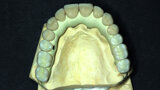

Fig. 11: Suprastructure cut out and transferred onto the model.